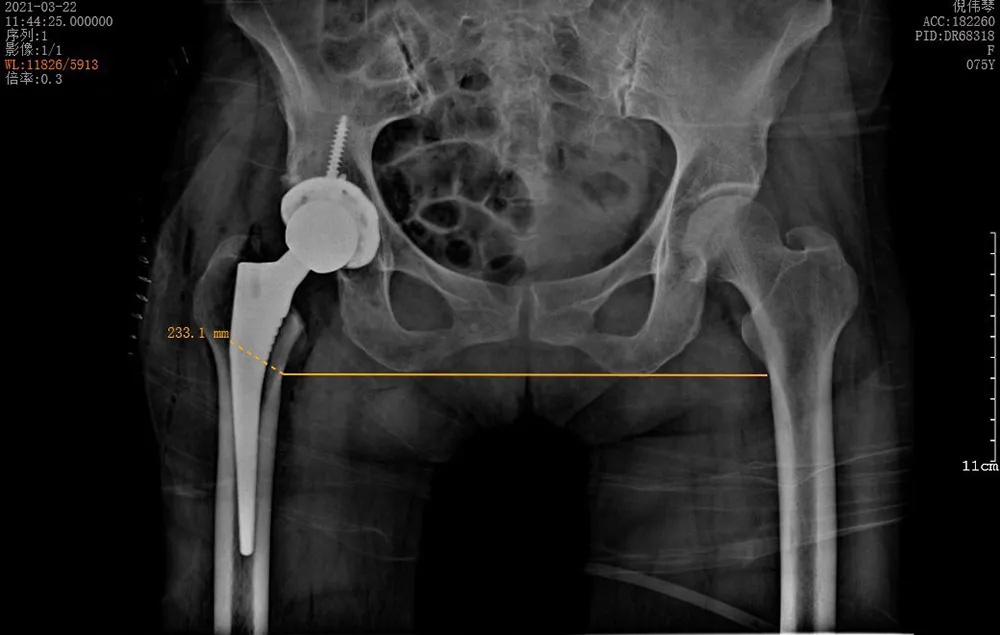

↑術(shù)后雙下肢完全等長

3月22日,在將倪阿姨的身體調(diào)整到最佳狀態(tài)并完善所有術(shù)前準備之后,羅軍團隊為她進行了手術(shù)。術(shù)中發(fā)現(xiàn)其股骨頭完全壞死,而且患者的骨質(zhì)疏松嚴重,所有操作必須十分小心,幸好有精準的AI-HIP術(shù)前規(guī)劃,手術(shù)歷時1個小時就成功完成,全程出血不到50ml。

術(shù)后第一天倪阿姨就能扶著助行器下地上廁所,已經(jīng)可以基本正常行走了。倪阿姨和家屬十分開心,連說:“想不到這么順利,術(shù)后這么快就可以走路了,而且髖關(guān)節(jié)不痛了!”